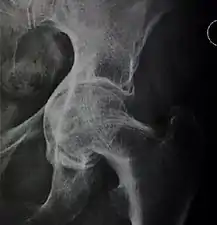

Crowe classification

In 1979 Dr. John F. Crowe et al. proposed a classification to define the degree of malformation and dislocation. Grouped from least severe Crowe I dysplasia to most severe Crowe IV.[13] This classification is very useful for studying treatment results.

Rather than using the Wiberg angle because it makes it difficult to quantify the degree of dislocation they used 3 key elements to determine the degree of subluxation: A reference line at the lower rim of the "teardrop", junction between the femoral head and neck of the respective joint and the height of the pelvis (vertical measurement). They studied anteroposterior pelvic x-rays and drew horizontal lines through the lower rim of a feature called "teardrop". The distance between this line and the middle lines of the junction between femur head and neck gave them a measure of the degree of femur head subluxation. They further established that a "normal" diameter of the femur head measures 20% of the height of the pelvis. If the middle line of the neck-head junction was more than 10% of the pelvis height above the reference line they considered the joint to be more than 50% dislocated.[13]

The following types resulted:[13]

| Class | Description | Dislocation |

| Crowe I | Femur and acetabulum show minimal abnormal development. | Less than 50% dislocation |

| Crowe II | The acetabulum shows abnormal development. | 50% to 75% dislocation |

| Crowe III | The acetabula is developed without a roof. A false acetabulum develops opposite the dislocated femur head position. The joint is fully dislocated. | 75% to 100% dislocation |

| Crowe IV | The acetabulum is insufficiently developed. Since the femur is positioned high up on the pelvis this class is also known as "high hip dislocation". | 100% dislocation |